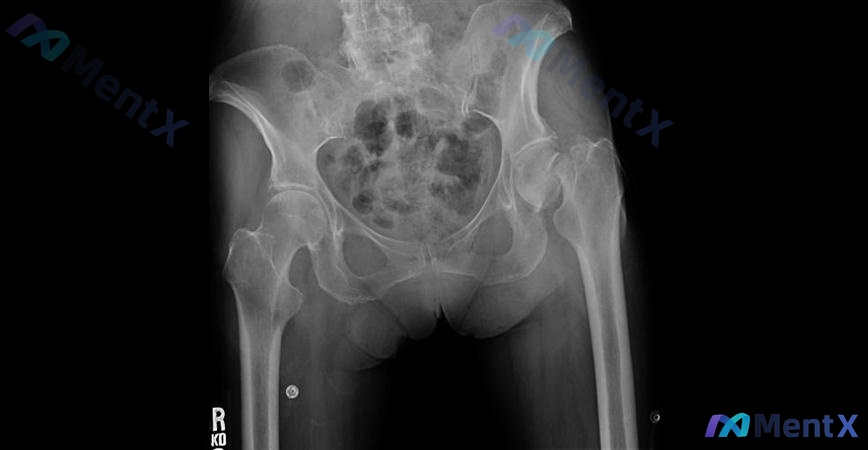

整理了一个骨科病例,大家来讨论一下治疗选择: 患者基本情况:79岁,活跃自行车手(这一点很重要),因事故就诊。 影像表现: - 左侧股骨颈皮质中断,有明显移位和成角,Shenton线中断 - 骨盆整体骨小梁稀疏、皮质变薄,提示骨质疏松背景 - 右侧髋关节、骶髂关节未见明显异常,腰椎有退行性变 - 未...